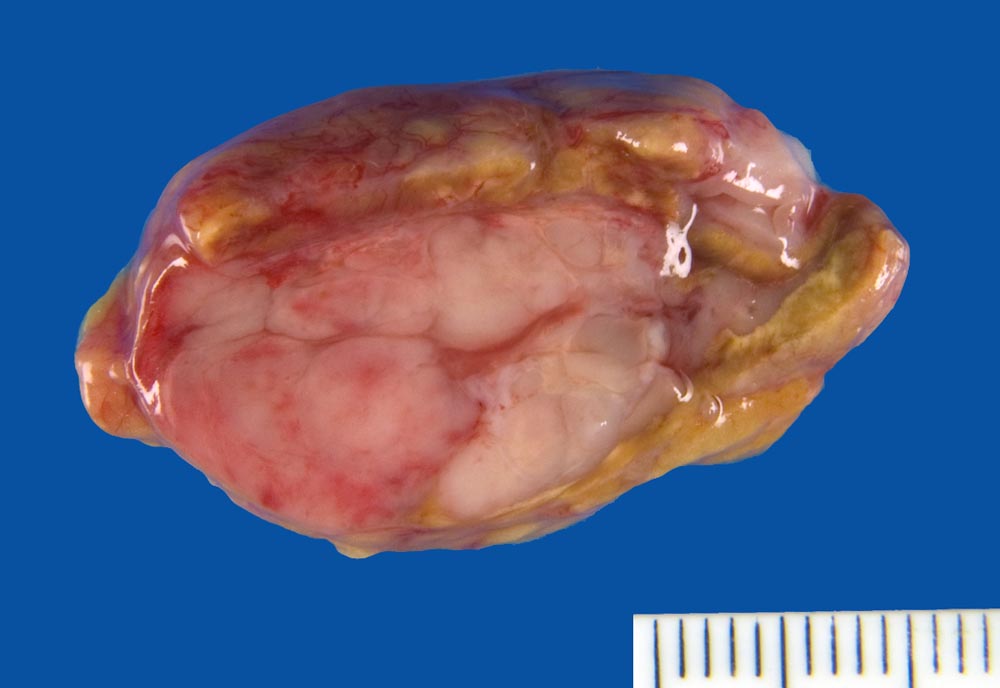

Infiltrate eines Plasmazellmyeloms in der Nebenniere

Nebenniere

Knotige weisse Tumorinfiltrate in der Nebenniere.

Autoptisch: Infiltration des Knochenmarks mit osteolytischen Herden im 5. Lendenwirbelkörper, Rippen, Beckenkamm, Sternum. Infiltration der Lunge links mit Schwerpunkt im Unterlappen, Infiltration der Pleura visceralis und parietalis links und der Pleura visceralis rechts. Seröse Pleuraergüsse (links: 3.3 l, rechts: 0.9 l). Mediastinaler Tumor (Dm 10cm) mit Übergreifen auf die Brustwand. Perikardinfiltraton. Infiltrate in Leber (Dm bis zu 3.5cm), Milz, Haut (Dm bis zu 0.8cm), Peritoneum, Nebenniere links, peripankreatische Lymphknoten, perirenales Weichteilgewebe.

Multiples Myelom IgG Kappa, Erstdiagnose vor 2 Jahren. Zustand nach 6 Zyklen Chemotherapie über 6 Monate und Radiotherapie vor 2 Jahren. Zustand nach 11 Zyklen Chemotherapie über 9 Monate und Radiotherapie über 2 Wochen bei mediastinalen und zervikalen Lymphknotenmetastasen seit 11 Monaten. Zustand nach rezividierenden malignen Pleuraergüssen seit 2 Monaten und Pleurapunktionen.